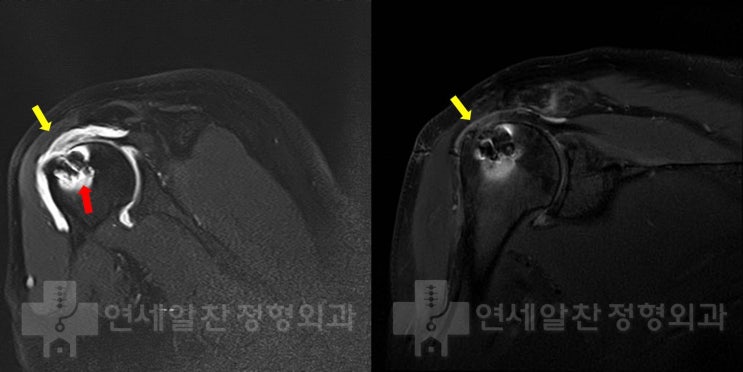

Rotator Cuff Revision Surgery and MegaDerm Augmentation After Re-tear Following Previous Repair

#rotator cuff#re-tear#revision surgery#MegaDerm augmentation#arthroscopy